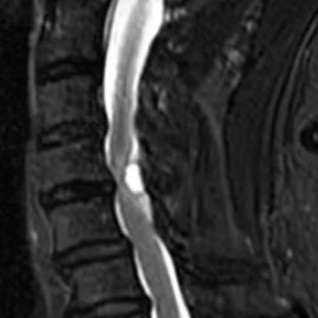

近日,奉贤区中心医院多学科团队紧密协作,成功救治一名因颈椎椎管内占位伴血肿形成、突发剧烈臂痛险些瘫痪的六旬患者。经精准诊断、精细手术及系统康复,患者一周内顺利康复出院,彰显区域医疗中心急危重症救治能力。 患者王老伯数日前突发右上臂剧烈放射性疼痛,右侧肢体迅速无力,持物、行走均受严重影响,病情进展极快。家人紧急将其送至区中心医院就诊。经初步检查,医生高度怀疑为颈椎椎管内占位性病变伴血肿形成。该病若脊髓长期受压,极易造成不可逆神经损伤,甚至导致瘫痪。 区中心医院随即启动多学科会诊(MDT),集结骨科、神经外科等相关科室专家进行联合评估。 神经外科团队率先为患者施行脊髓血管造影,明确病灶位置与范围,排除脊髓血管畸形的可能,为后续手术方案的制定提供了精准依据。 然而术前评估带来了新难题:王老伯还合并有睡眠呼吸暂停综合征与阻塞性肺病,这增加了手术与麻醉的风险。呼吸与危重症医学科随即为其量身定制了呼吸调理方案,并指导术前呼吸训练;耳鼻咽喉科协助排查气道梗阻隐患,优化呼吸道管理策略。在多学科协作下,王老伯的呼吸功能被调整至可耐受手术的状态。 颈椎手术被誉为脊柱外科“皇冠上的明珠”。颈椎椎管内部空间狭窄,神经结构密集,加之肿物与神经粘连紧密,手术操作难度极大。骨科林在俊主任医师团队综合多学科会诊意见,经过反复研讨,最终制定了个性化的精细手术方案。 手术当天,麻醉科团队精准实施麻醉,并全程动态监测患者生命体征;手术室护理团队默契配合,严格执行无菌操作,为手术安全保驾护航。在多学科团队的紧密协作下,林在俊主任医师在手术显微镜下以毫米级精度逐步操作,完整清除了肿物及血肿,并切开硬膜进行探查,确保无病灶残留。手术在最大程度保护神经功能与脊柱稳定性的前提下顺利完成,术中出血少,创伤小。 术后第二天,患者臂痛明显缓解,可自主翻身、抬手。疼痛理疗科同步开展个体化康复训练,术后一周,患者已能独立行走、生活自理,顺利康复出院。 专家提醒:这些信号别当“小毛病” 颈肩腰腿痛不可轻视。如出现突发剧烈疼痛、肢体麻木无力、步态不稳等症状,可能是椎管内病变信号,务必尽早到正规医院就诊,避免延误最佳治疗时机。 专家信息 各种复杂脊柱疾患的手术治疗及微创治疗。尤其擅长:脊柱肿瘤手术治疗及综合治疗;椎管内(外)肿瘤切除手术;各种颈、腰椎疾患(包括颈椎病、腰椎间盘突出症、椎管狭窄症、腰椎滑脱症等)及脊柱骨折的微创治疗。 奉贤区中心医院骨科 专家门诊信息一览 上海市第六人民医院 *根据出诊时间排序 奉贤区中心医院 *根据出诊时间排序 门诊预约电话 021-375385222(8:00—16:00)

更多精彩内容,请关注“美谷奉贤”APP

从射击到索降,直击奉贤特警春日“硬核”练兵场

服务升级,就在家门口!四团镇镇西村“中医特色卫生室”提档升级、全新亮相!